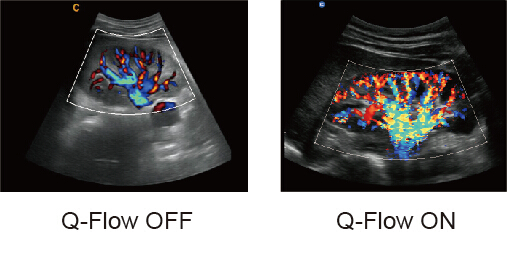

Q-flow

● Esta tecnología de detección de color adaptativo puede ajustar automáticamente la evaluación de la señal de color y ruido según los diferentes tejidos.

● Como resultado, la sensibilidad al color del flujo de baja velocidad es significativamente mayor.